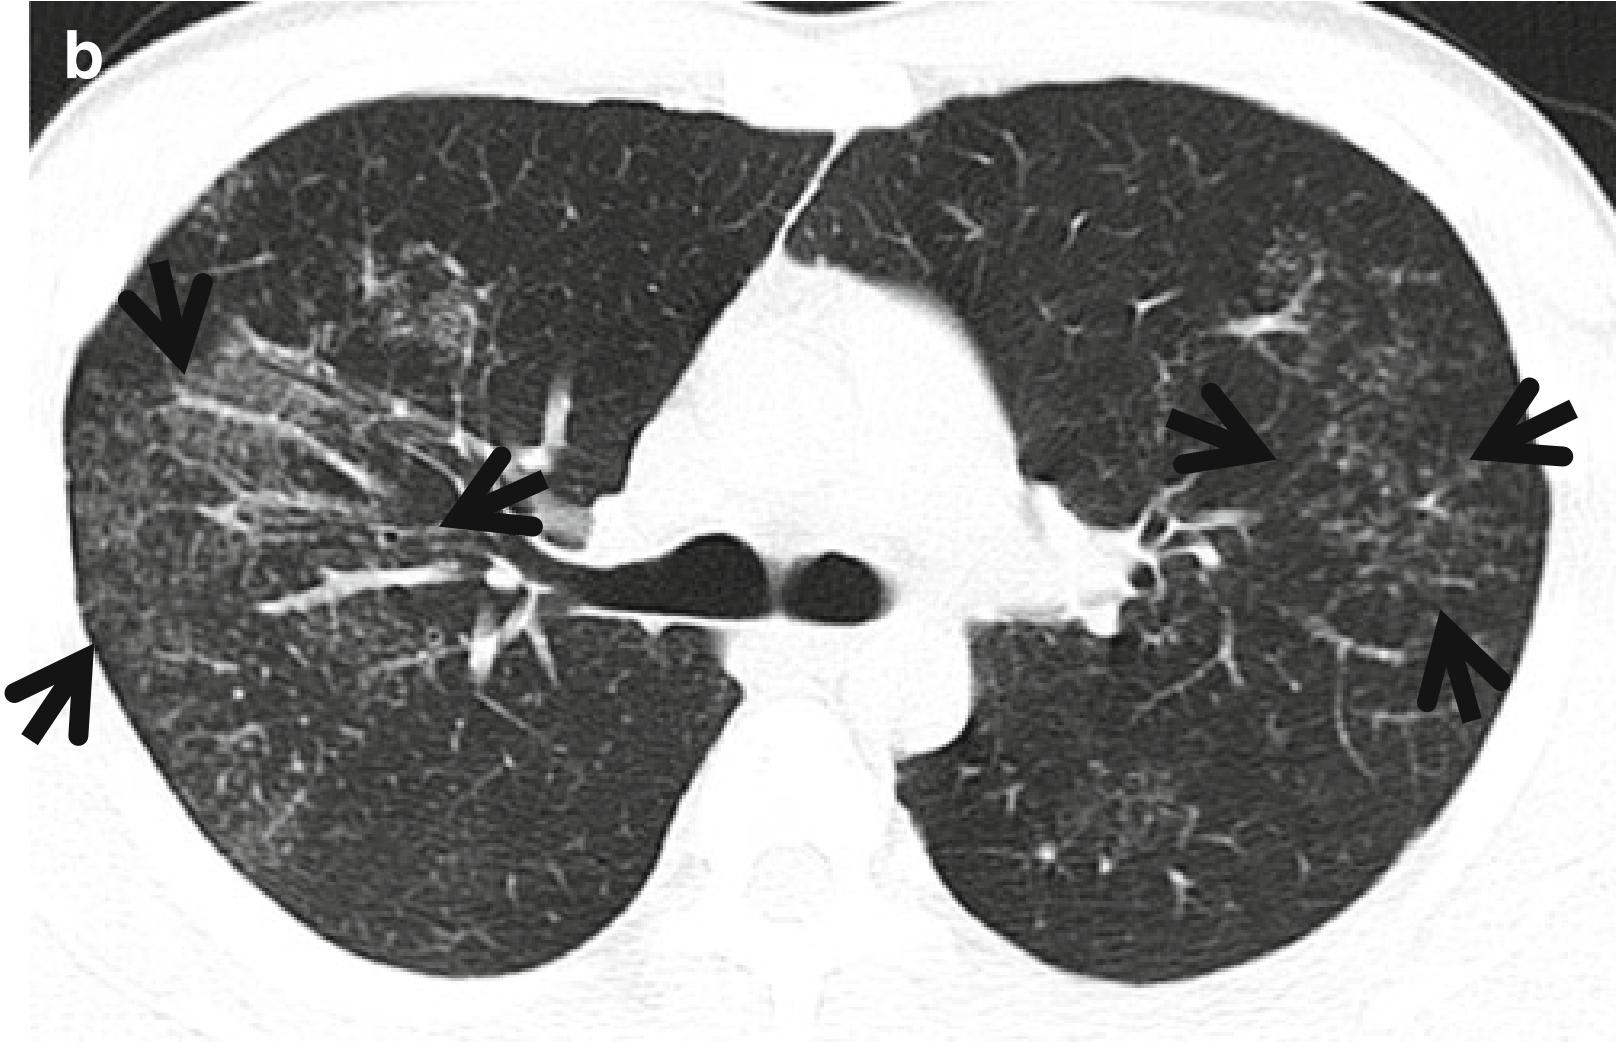

图2 CT星系征。

患者男性,44 岁,活动性肺结核。

(a.b)连续CT扫描(层厚=5.0 mm,低剂量模式)于右中间段支气管水平,可见左肺上叶上舌段CT星系征(箭头所示)。在层厚相对较厚的CT图像上。需要注意的是,不能把星系征看成磨玻璃密度影而诊断为浸润性肺腺癌。

(c)左肺上叶外科活检大体病理标本;可见多发结节状小肉芽肿相互聚集(箭头所示)。

(d)低倍光镜(×4)下可见:细支气管周围间质内见聚集的多发肉芽肿结节、其中心可见坏死。肉芽肿向心性汇聚,外围较分散。Br.细支气管。